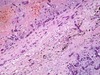

22

* caseation necrosis and fibrosis

* can't tell that this is lung (but was)